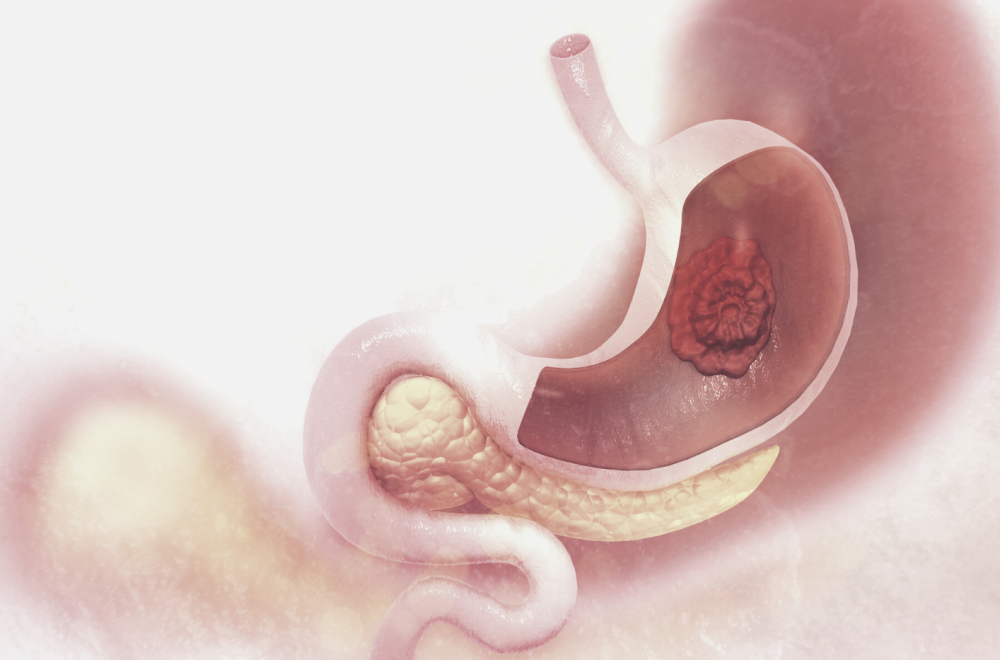

Рак желудка

Рак желудка — злокачественная опухоль, которая образуется из клеток слизистой органа.